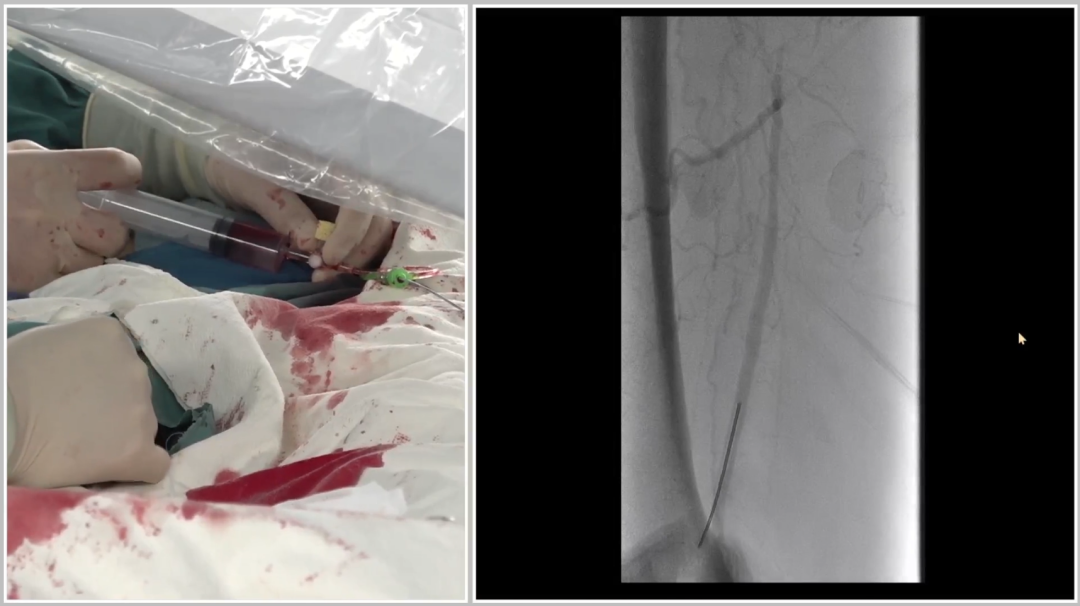

远端困境:

内膜下难以返回真腔,果断选择逆穿

导丝进入远端内膜下后,反复尝试返回真腔失败。为避免过度操作损伤远端流出道,团队决定行逆向穿刺(逆穿):

调整球管至左前斜20°~30°,在路图下定位穿刺点;

近端推注造影剂,透视下确认血管位置,穿刺成功(可见明显充盈缺损);

跟进V18导丝突破远端纤维帽,配合支撑导管完成对接。

逆穿的难点在于选择合适的对接位置,对接判断要点是导丝成袢后,通过近端Terumo导丝触碰,若有明显"碰触感",提示位于同一内膜下,可确认对接。